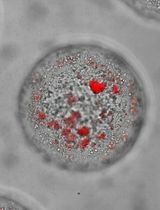

Many new drug development candidates are highly lipophilic compounds with low water solubility. This constitutes a formidable challenge for the use of such compounds for cancer therapy, where high doses and intravenous injections are needed (Di et al., 2012). Here, we present a poly(2-oxazoline) polymer (POx)-based nanoformulation strategy to solubilize and deliver hydrophobic drugs. POx micelles are prepared by a simple thin-film hydration method. In this method, the drug and polymer are dissolved in a common solvent and allowed to mix, following which the solvent is evaporated using mild heating conditions to form a thin film. The micelles form spontaneously upon hydration with saline. POx nanoformulation of hydrophobic drugs is unique in that it has a high drug loading capacity, which is superior to micelles of conventional surfactants. Moreover, multiple active pharmaceutical ingredients (APIs) can be included within the same POx micelle, thereby enabling the codelivery of binary as well as ternary drug combinations (Han et al., 2012; He et al., 2016).

Recent statistics show that only 3.7% of the new drug candidates that enter clinical testing are approved for use in cancer treatment. This has been primarily attributed to the poor pharmacokinetics of poorly water-soluble drug candidates, which results in suboptimal performance (Gala et al., 2020). POx polymeric micelles offer several advantages over traditional drug delivery systems such as liposomes, microparticles, and nanogels, among others. The unparalleled high solubilizing capacity of POx micelles for a large variety of hydrophobic drugs enables the delivery of greater amounts of drugs with a substantially lesser amount of excipient (Luxenhofer et al., 2010, He et al., 2016). POx-based drug formulations are easy to prepare, safe, and stable. Additionally, a quantitative structure-property relationship (QSPR) model has been developed to predict drug loading into POx micelles, which can be utilized to facilitate high throughput screening of sparingly soluble drug development candidates for incorporation in POx micelles (Alves et al., 2019).